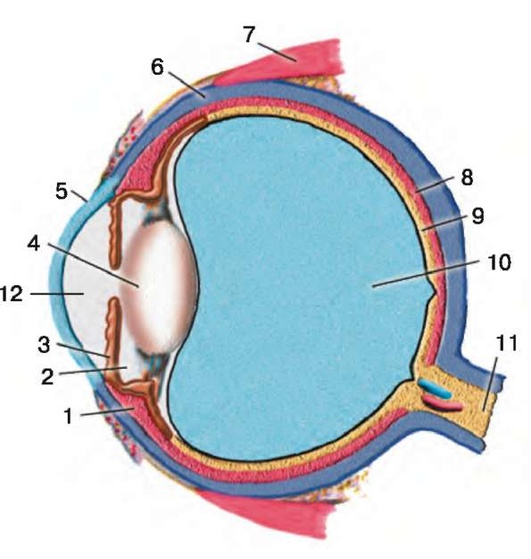

Рис. 1.1. Глазное яблоко (сагиттальный разрез): 1 - ресничное тело; 2 - задняя камера; 3 - радужка; 4-хрусталик; 5 - роговица; 6 - склера; 7 - верхняя прямая мышца, 8 - собственно сосудистая оболочка (хориоидея); 9 - сетчатка; 10 - стекловидное тело; 11 - зрительный нерв; 12 - передняя камера